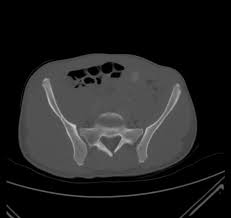

Anterior Superior Iliac Spine, Appendicular Skeleton And Joints Ppt Download : It can be palpated by putting the hands at the top of the hipbones and following the bony margins toward the front of the hips.. The posterior border of the ala, shorter than the anterior, also presents two projections separated by a notch, the posterior superior iliac spine and the posterior inferior iliac spine. Jun 28, 2021 · insertion: Asis, anterior superior iliac spine. Diagnosis is made with pelvis radiographs that shows an avulsion off the aiis. Anterior angulation of the coccyx may be a normal variant but poses a diagnostic challenge for those considering coccygeal trauma.

It provides attachment for the inguinal ligament , the sartorius muscle , 1 4 and the tensor fasciae latae muscle. The anterior superior iliac spine (asis) is the most anterior part of the iliac crest. An anterior superior iliac spine (asis) avulsion is a traumatic avulsion of the asis due to a sudden and forceful contraction of the sartorius and tensor fascia lata that occurs in young athletes. Asis, anterior superior iliac spine. This part is the most observable and palpable of the pelvis. The posterior border of the ala, shorter than the anterior, also presents two projections separated by a notch, the posterior superior iliac spine and the posterior inferior iliac spine. Diagnosis is made radiographically with displaced injuries but ct/mri may be required to diagnosis nondisplaced fractures. It provides attachment for the inguinal ligament, and the sartorius muscle. An anterior inferior iliac spine (aiis) avulsion is an apophyseal avulsion injury seen in adolescent athletes as a result of eccentric contraction of the rectus femoris. It refers to the anterior extremity of the iliac crest of the pelvis. The anterior superior iliac spine refers to the anterior extremity of the iliac crest of the pelvis. Outer lip of anterior iliac crest, anterior superior iliac spine (asis) insertion: Classification four types of coccyx have been described:

Outer lip of anterior iliac crest, anterior superior iliac spine (asis) insertion: Aug 29, 2017 · aiis, anterior inferior iliac spine; Asis, anterior superior iliac spine. The posterior border of the ala, shorter than the anterior, also presents two projections separated by a notch, the posterior superior iliac spine and the posterior inferior iliac spine. An anterior superior iliac spine (asis) avulsion is a traumatic avulsion of the asis due to a sudden and forceful contraction of the sartorius and tensor fascia lata that occurs in young athletes. The tensor fasciae latae and sartorius muscles of the thigh have their origins at the anterior superior spine. An anterior inferior iliac spine (aiis) avulsion is an apophyseal avulsion injury seen in adolescent athletes as a result of eccentric contraction of the rectus femoris. It provides attachment for the inguinal ligament, and the sartorius muscle. The posterior superior iliac spine serves for the attachment of the oblique portion of the posterior sacroiliac ligaments and the multifidus. It provides attachment for the inguinal ligament , the sartorius muscle , 1 4 and the tensor fasciae latae muscle. It can be palpated by putting the hands at the top of the hipbones and following the bony margins toward the front of the hips. Classification four types of coccyx have been described: Diagnosis is made radiographically with displaced injuries but ct/mri may be required to diagnosis nondisplaced fractures.

The coccyx is curved slightly forward, with its. It can be palpated by putting the hands at the top of the hipbones and following the bony margins toward the front of the hips. Outer lip of anterior iliac crest, anterior superior iliac spine (asis) insertion: Diagnosis is made with pelvis radiographs that shows an avulsion off the aiis. Jun 09, 2015 · at the posterior end of the ilium, the iliac crest narrows before terminating at another bony process known as the posterior superior iliac spine. Anterior angulation of the coccyx may be a normal variant but poses a diagnostic challenge for those considering coccygeal trauma. Anterior aspect of greater trochanter of femur innervation: It provides attachment for the inguinal ligament , the sartorius muscle , 1 4 and the tensor fasciae latae muscle. The posterior superior iliac spine serves for the attachment of the oblique portion of the posterior sacroiliac ligaments and the multifidus. The tensor fasciae latae muscle attaches to the lateral aspect of the superior anterior iliac spine, and also about 5 cm away at the i. An anterior superior iliac spine (asis) avulsion is a traumatic avulsion of the asis due to a sudden and forceful contraction of the sartorius and tensor fascia lata that occurs in young athletes. Thigh abduction, thigh internal rotation (anterior part); Jun 28, 2021 · insertion: